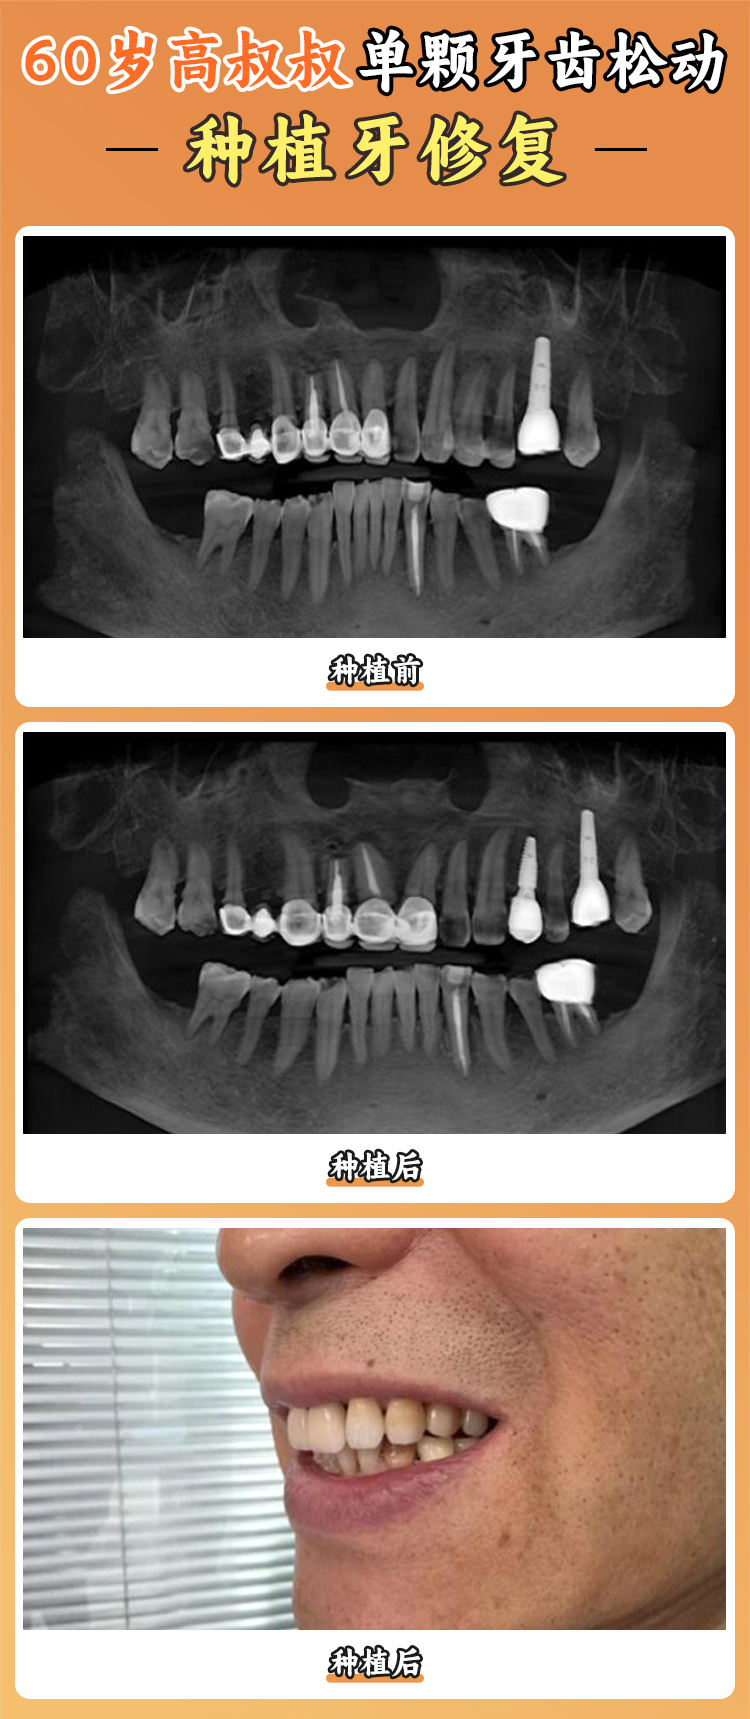

1. 种植科技术精良:种植科是新乡植得口腔医院的特色科室之一。这里开展了多项新型种植技术,像即刻种植、全口/半口种植等。即刻种植技术呢,就是在拔牙后马上进行种植,减少了患者的等待时间,也能更好地保存牙槽骨。全口/半口种植技术对于那些牙齿缺失比较多的患者来说,简直是福音。医院在这些种植技术上积累了丰富的临床经验,已经成功帮助特别多患者修复了牙齿功能。